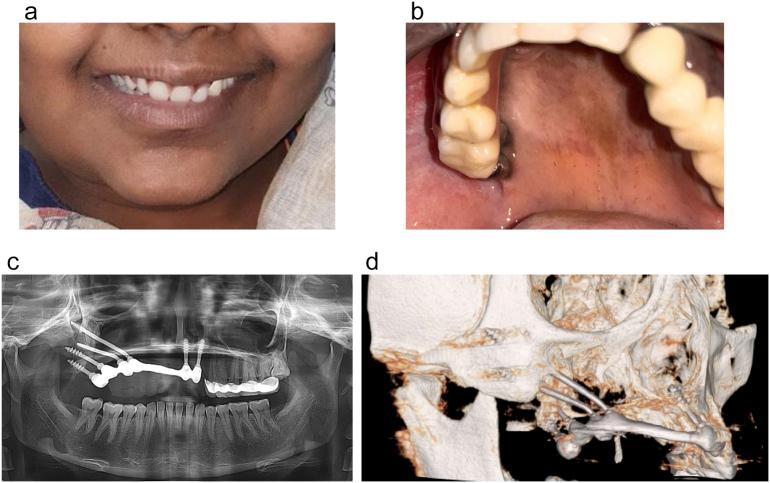

A 20-year-old female patient presented to the clinic following hemimaxillectomy with soft tissue approximation one year ago. The patient was very depressed and reported high aesthetic concern and masticatory inefficiency and required a fixed prosthesis. A multidisciplinary team was formed. A panorama and cone beam CT were acquired. The treatment plan included the construction of an immediately loaded, fixed implant-supported reconstructive prosthesis using 6 Corticobasal® implant (BCS® and ZDI® implant designs, Dr. Ihde Dental AG, Switzerland) and a follow up program. After 3 years in function, the patient presented with 100 % implant survival rate, no complaints, and reported great improvement in esthetics, speech, mastication, and quality of life.

一名20岁女性患者在一年前接受半侧上颌骨切除及软组织贴合术后前来就诊。患者非常沮丧,报告了对美观的高度关注和咀嚼效率低下的问题,需要一副固定假体。组建了一个多学科团队。拍摄了全景片和锥形束CT。治疗计划包括使用6枚皮质基底®种植体(BCS®和ZDI®种植体设计,瑞士伊德牙科股份公司)构建即刻负重的、固定种植体支持的重建假体以及后续跟进计划。在功能使用3年后,患者种植体存活率达100%,无任何不适主诉,并报告在美观、言语、咀嚼和生活质量方面有了很大改善。